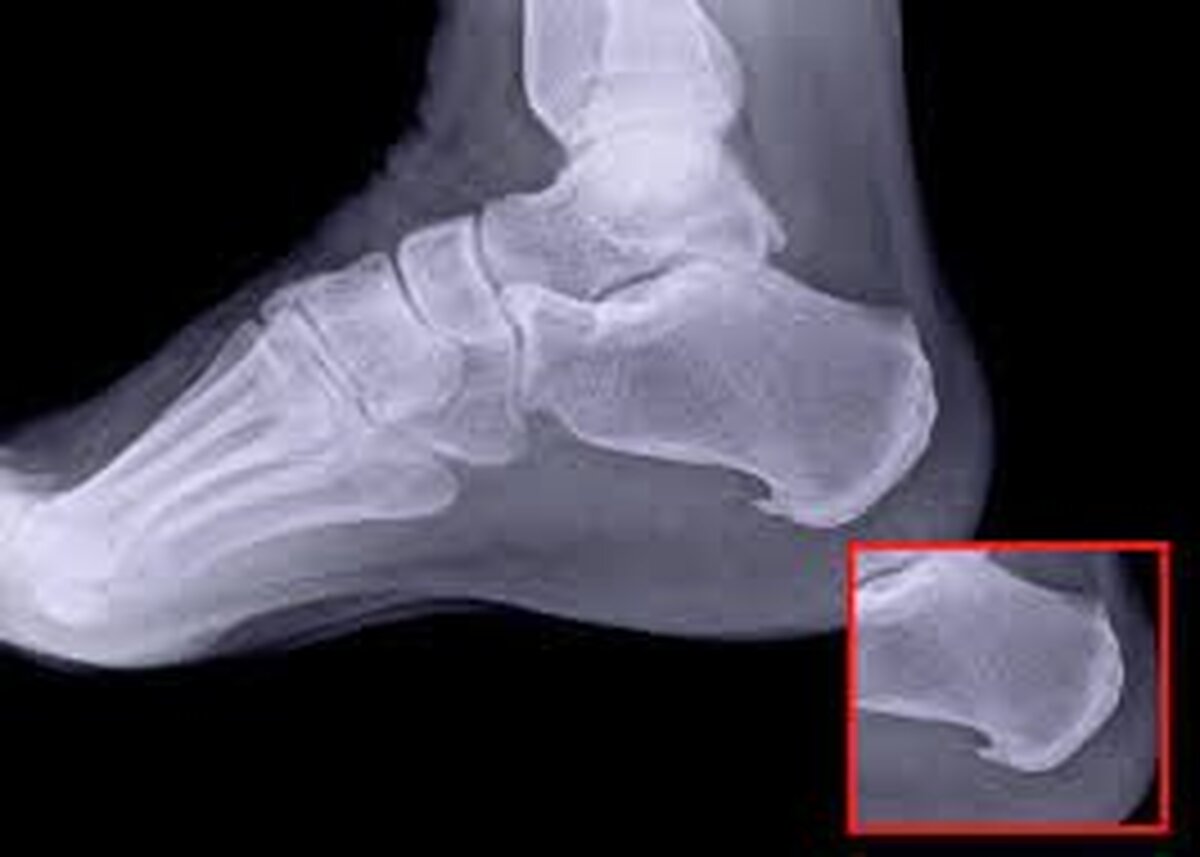

خار پاشنه یا خار استخوانی، زائده‌ای استخوانی است که از پایین پاشنه پا، جایی که استخوان پاشنه به رباط بین پاشنه و قسمت برجسته پا (فاسیا یا نیام کف پا) متصل می‌شود، بیرون می‌زند.

تشخیص

پزشک معمولاً پای شما را معاینه می‌کند و در مورد فعالیت بدنی که ممکن است باعث درد پاشنه شما شده باشد، سؤال می‌کند. در نهایت، عکس‌برداری با اشعه ایکس یکی از رایج‌ترین آزمایش‌هایی است که ارائه دهندگان خدمات درمانی برای تشخیص خار پاشنه استفاده می‌کنند.